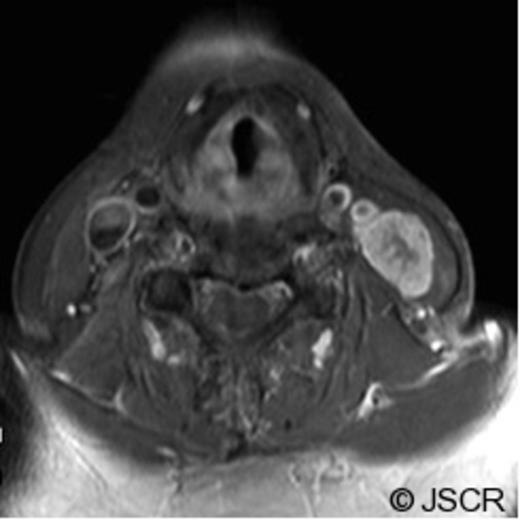

On examination, she had a 3 cm, firm and horizontally mobile neck mass intimate to her cervical incision line in the left mid-sternocleidomastoid region. FNA biopsy was performed and was consistent with chordoma. The patient underwent repeat staging with magnetic resonance imaging (MRI) of the head and neck (Figure 1), as well as computed tomography (CT) of the chest, abdomen and pelvis.

MR and CT Neck findings of the surgical pathway recurrence of a clival chordoma. (Axial, T1-weighted with Gadolinium MR image). Image obtained at the time of presentation with the neck mass, show a large, heterogeneous level III neck mass (23 mm x 17mm) with infiltration throughout the sternocleidomastoid muscle without obvious invasion of the great vessels. A few surrounding rounded lymph nodes within normal size limits are seen.